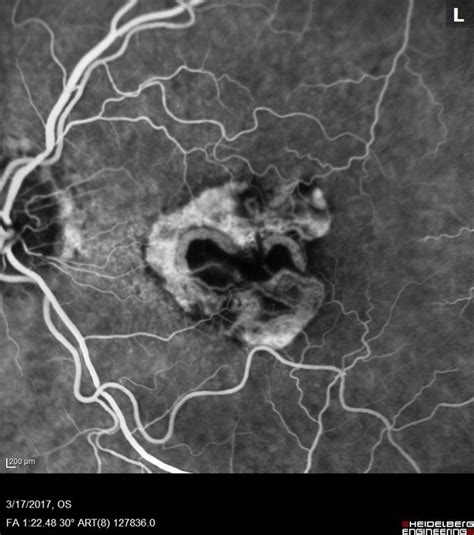

Diagnostic tools such as fluorescein angiography (FA) and optical coherence tomography (OCT) are essential for identifying and monitoring active CNV. FA involves injecting a dye into the bloodstream and taking pictures of the retina to visualize the blood vessels and any leakage. OCT is a non-invasive imaging technique that provides detailed cross-sectional images of the retina, allowing doctors to see the structure of the macula and identify any fluid accumulation or abnormalities. Monitoring the activity of CNV helps ophthalmologists adjust treatment plans to optimize outcomes and prevent further vision loss.